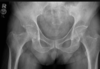

Masculino, 12 anos

Síndrome da sincondrose isquiopúbica assimétrica (Doença de Van Neck-Odelberg)

Variante da normalidade (em geral assintomático)

Crianças

Alargamento e radioluscência na sincondrose isquiopúbica, que simula neoplasias, infecção;